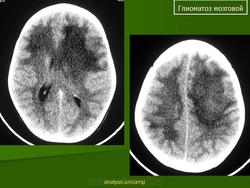

Глиоматоз мозговой. Ср, 03/09/2014 - 12:08 #1 Катенёв Валенти... Не на сайте Был на сайте: 7 лет 3 месяцев назад Зарегистрирован: 22.03.2008 - 22:15 Публикации: 54876 Продолжение.Приложения:

Продолжение.